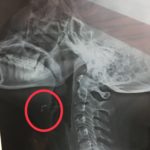

先日、ルイという魚のカレーを昼ごはんにいただきました。

ルイとはバングラデシュの川魚で、こんな感じの魚 ...